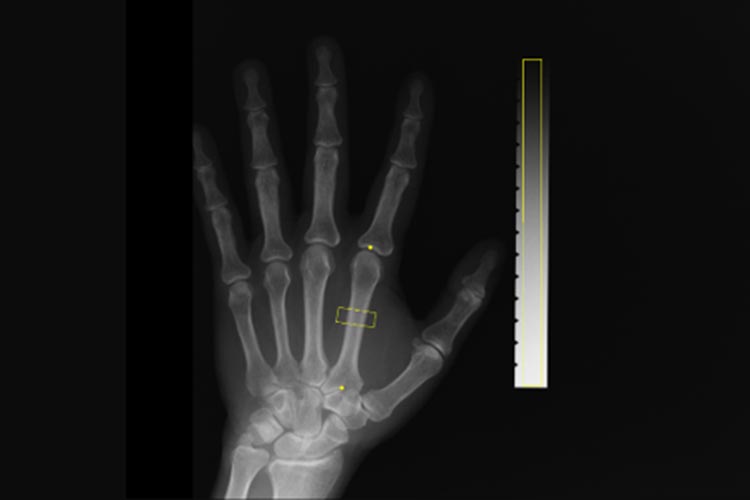

レントゲン検査

座位や臥位で撮影することも可能です。当院では医師の診断支援を行うAIを導入しています。専門医による読影にAIの技術を加えることで異常の見落としの防止に積極的に取り組んでいます。